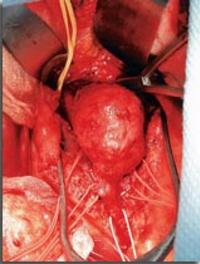

Depuis la publication princeps de Charles Dubost en 1951, on peut traiter chirurgicalement les anévrysmes de l’aorte abdominale (AAA). [...]